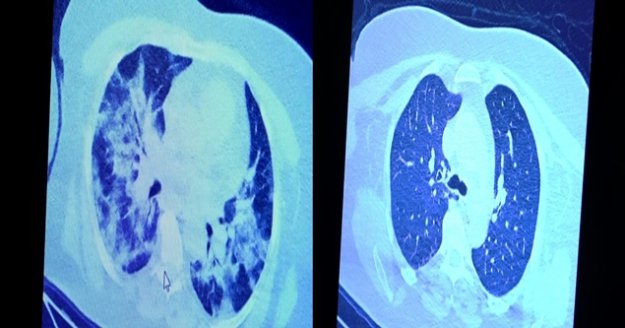

VM Medical Park Hastanesi’nde görev yapan Göğüs Hastalıkları Kliniği’nden Prof. Dr. Şevket Özkaya da bir hafta ilaç kullanmayan bir pozitif hastanın akciğer tomografisini inceledi. Hasta pozitif haldeyken ilk akciğer tomografisine bakıldı. Tomografide akciğerlerdeki tutulmanın az olduğu gözlemlendi. Akabinde aynı hastanın verilen ilaçları kullanmamış ve 1 hafta boyunca tedaviye uymamış haldeki akciğer tomografisine bakıldı. Sonuç ise ilaç kullanımının önemini ortaya çıkardı. Hastanın akciğer tomografisinde yaygın buzlu camların ve hava yollarının hava yerine ciddi şekilde sıvı ile dolduğu gözlemlendi.

Akciğer tomografisinde oluşan değişim ile ilgili bilgi veren Prof. Dr. Şevket Özkaya, "Ekranda 55 yaşında bir kadın hastamızın filmini görüyorsunuz. Bu kadın hastamız acil servisimize ateş şikâyetiyle geldi ve korona virüsünden şüphe ettik. Testini yaptığımızda ise testin sonucu pozitif geldi. Tomografi çektiğimiz zaman akciğerlerinde henüz ciddi bir tutulum görünmezken hastamız 55 yaşında olduğu için her an ilerleyebilir korkusuyla Sağlık Bakanlığımızın önerdiği ilaçları ve reçeteyi hastanemizden kendisine verdik. Hasta kendini evde karantinaya aldı fakat sonradan öğrendik ki tereddüt ettiği için ilaçlarını kullanmayarak kendini evde tedavisiz bırakmış. Yaklaşık bir hafta sonra aynı hasta acil servisimize bu sefer solunum yetmezliği şikâyetiyle geldi. Solunum yetmezliği gelişince hastanın akciğer tomografisinde ‘buzlu cam’ dediğimiz ve daha ileri konsolide alanların oluştuğunu gördük. Yaygın akciğer harabiyeti dediğimiz bir tablo oluşmuştu. Bu durumda hastada solunum yetmezliği olduğu için yoğun bakıma almak zorunda kaldık" dedi.